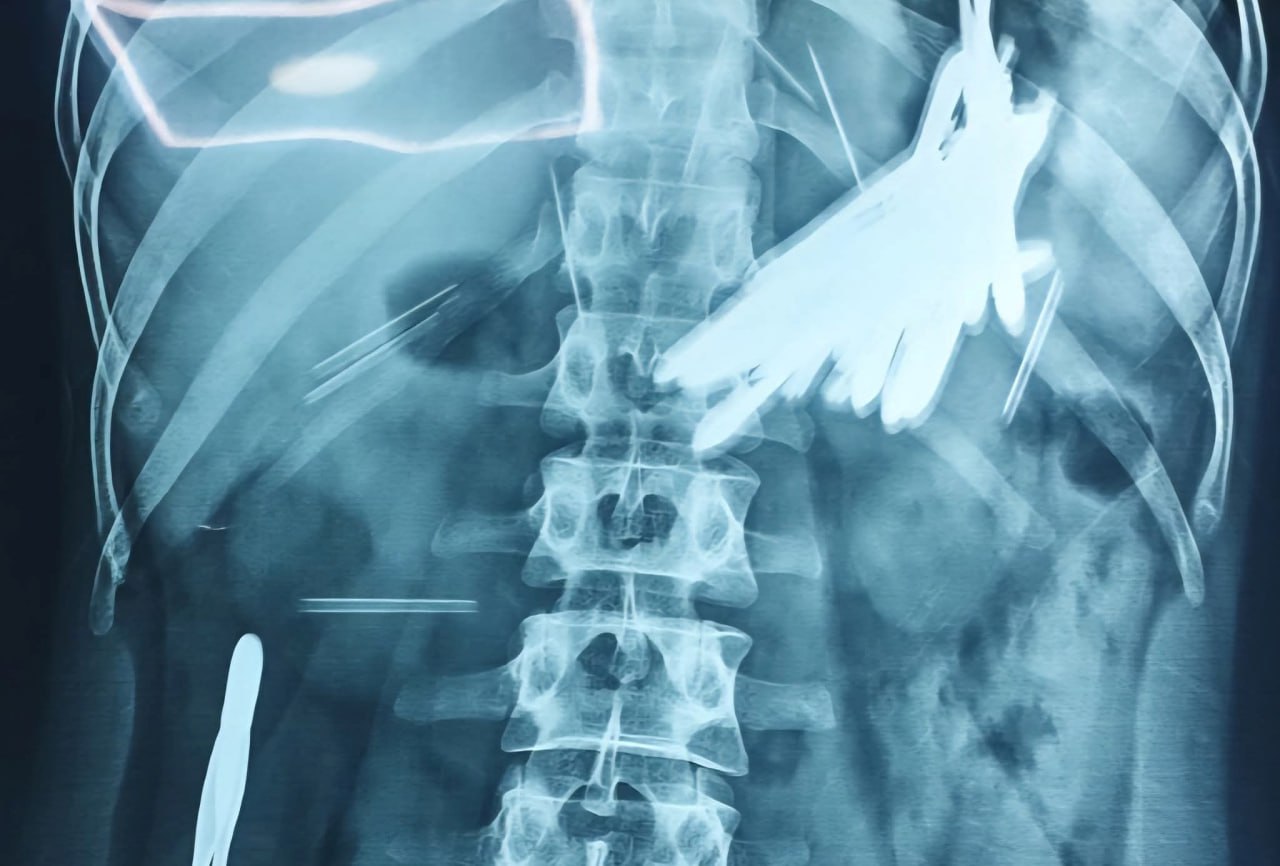

لە نەشتەرگەرییەكدا لەلایەن تیمی پزیشكی بەشی هەناوبینی و بێهۆشكاری نەخۆشخانەی كۆئەندامی هەرس و جگەر لە شاری سلێمانی 16 موكێش و 8 دەرزی لە جەستەی پیاوێكی تەمەن 29 ساڵ دەرهێنرا.